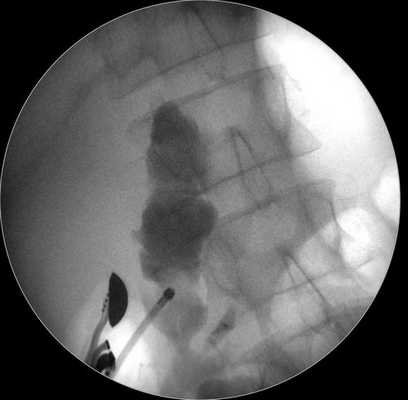

3. Электрокоагуляция тканей желудка и стенки кисты с последующей цистотомией стенки кисты посредством 8,5 Ch цистотома (MTWEndoscopieManufaktur, Germany) (рис. 2). Рис. 2. Цистотомия стенки кисты устройством МТW (MTW Endoscopie Manufaktur, Германия) (случай 1).

С помощью ультразвуковой навигации определяется безопасная траектория для внутреннего дренирования кисты. В инструментальный канал специального эхо-эндоскопа проводится цистотом, посредством которого формируется соустье между луковицей двенадцатиперстной кишки и просветом кисты (рис. 5 а, б).